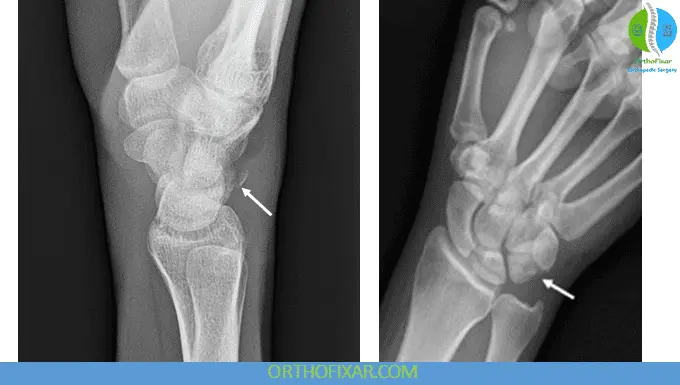

Radiographic Evaluation

Accurate imaging is critical but can be challenging:

- Posteroanterior (PA) View

Useful for identifying transverse fractures of the triquetral body. - Standard AP and Lateral Views

Often insufficient for detecting dorsal chip fractures due to superimposition by the lunate. - Oblique or Pronated Lateral View

Enhances visualization of dorsal cortical fractures and is strongly recommended when clinical suspicion persists.

Advanced imaging such as CT may be considered in equivocal cases or for surgical planning.